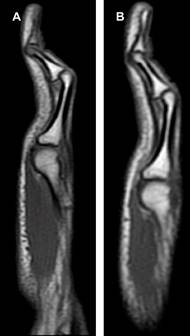

Masculino de 15 años de edad, que presenta deformidad del dedo meñique de ambas manos. No tiene antecedentes de traumatismos, patologías o síndromes congénitos. Nadie más en su familia presentaba dicha morfología en los dedos. En el estudio de resonancia magnética (RM) se observó deformidad del quinto dedo por hiperflexión de la articulación interfalángica proximal en forma bilateral (Figura 2). El vientre muscular del cuarto lumbrical presenta un curso superficial en relación a los tendones flexores superficial y profundo, secundario a una inserción anómala, con disminución en su diámetro en el plano axial (Figura 3). Todos los hallazgos son más evidentes en el dedo meñique de la mano derecha. Las articulaciones interfalángicas distales y metacarpofalángicas presentan hiperextensión compensatoria.

Resonancia magnética axial T1 a nivel de la articulación metacarpofalángica, de la mano derecha (A) e izquierda. (B) Inserción aberrante del cuarto músculo lumbrical (flecha azul) hacia el tendón flexor superficial del cuarto dedo (asterisco rojo), con curso más superficial de lo habitual. Disminución en el grosor del vientre muscular del cuarto lumbrical, más evidente en la mano izquierda. Tendón superficial y profundo del quinto dedo (asterisco amarillo).

Figura 3:

Favril y colaboradores publicaron una serie de tres casos con imágenes de RM y ultrasonido, donde identificaron que los músculos lumbricales son la principal estructura afectada. Estos músculos pueden tener una inserción aberrante hacia el tendón flexor superficial, un curso aberrante o una disminución en su grosor o longitud.1

Actualmente la RM es de gran utilidad, no sólo en la valoración de las alteraciones de los músculos lumbricales, sino también en otras estructuras relacionadas con la deformidad como los tendones flexores superficiales y profundos, la placa volar, los ligamentos colaterales y tejidos blandos superficiales.